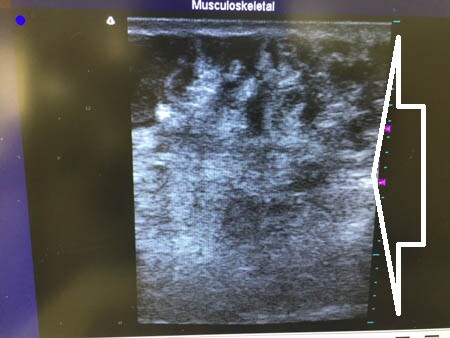

右腰。

↓ ↓ ↓